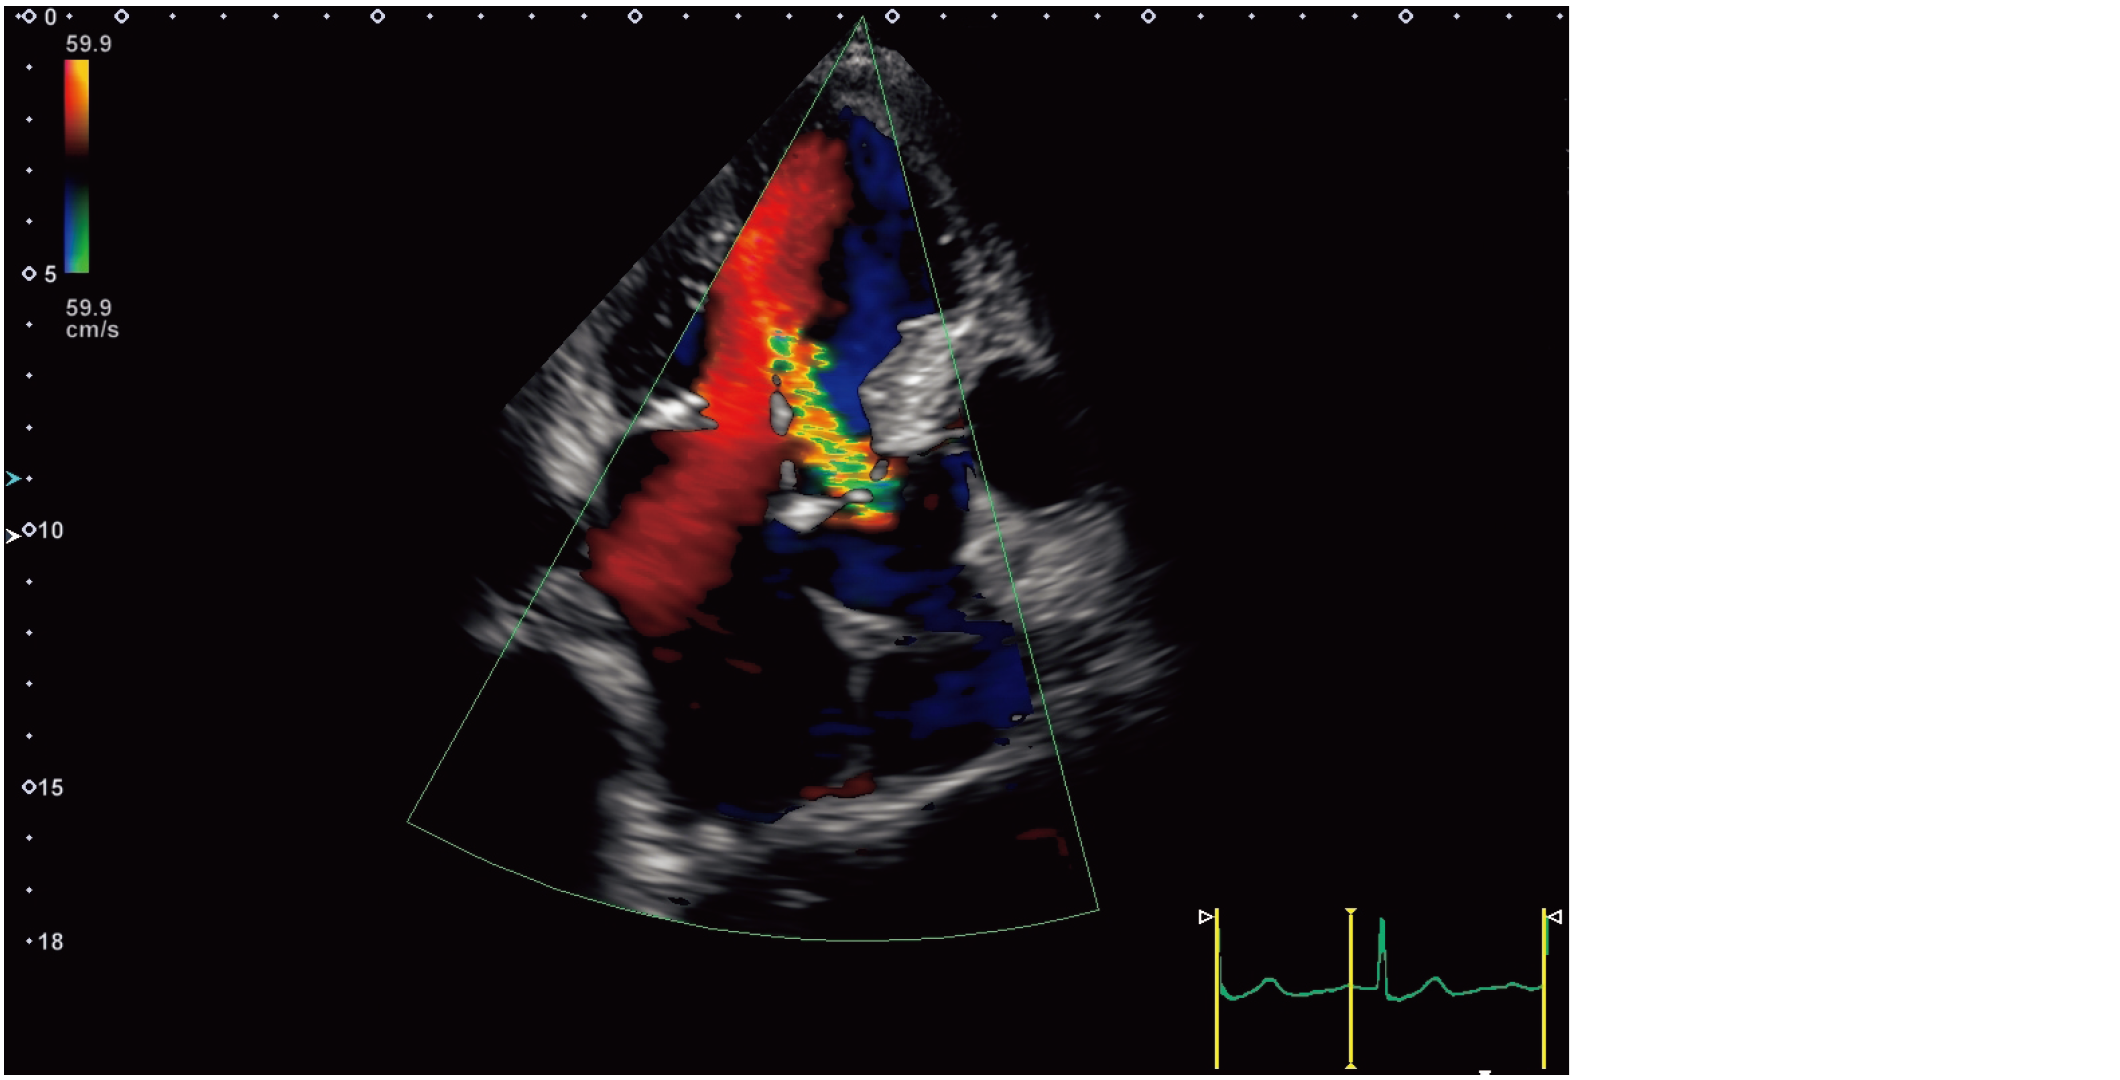

心尖部長軸像のカラードプラ像を示す。

最も考えられるのはどれか。

• 1. 僧帽弁狭窄症

• 2. 大動脈弁狭窄症

• 3. 心室中隔欠損症

• 4. 僧帽弁閉鎖不全症

• 5. 大動脈弁閉鎖不全症